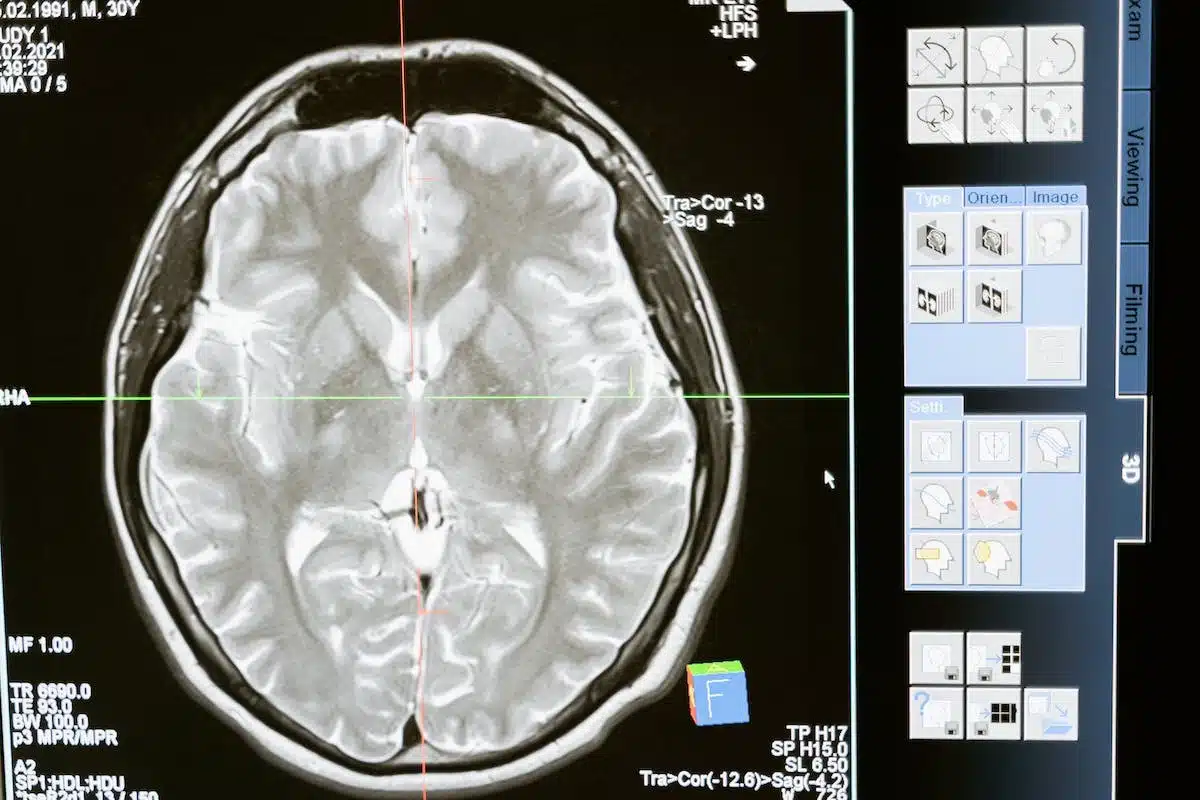

Les examens d’imagerie sont souvent indispensables pour confirmer une hypothèse diagnostique. Parmi les plus courants :

- Radiographie : utile pour détecter les fractures ou les malformations osseuses.

- IRM (Imagerie par Résonance Magnétique) : permet de visualiser les tissus mous, comme les tendons et les ligaments, et de détecter des pathologies comme la tendinite ou le névrome de Morton.

- Échographie : non invasive, elle offre une bonne visualisation des structures superficielles et permet d’identifier des lésions telles que les entorses ou les infections.